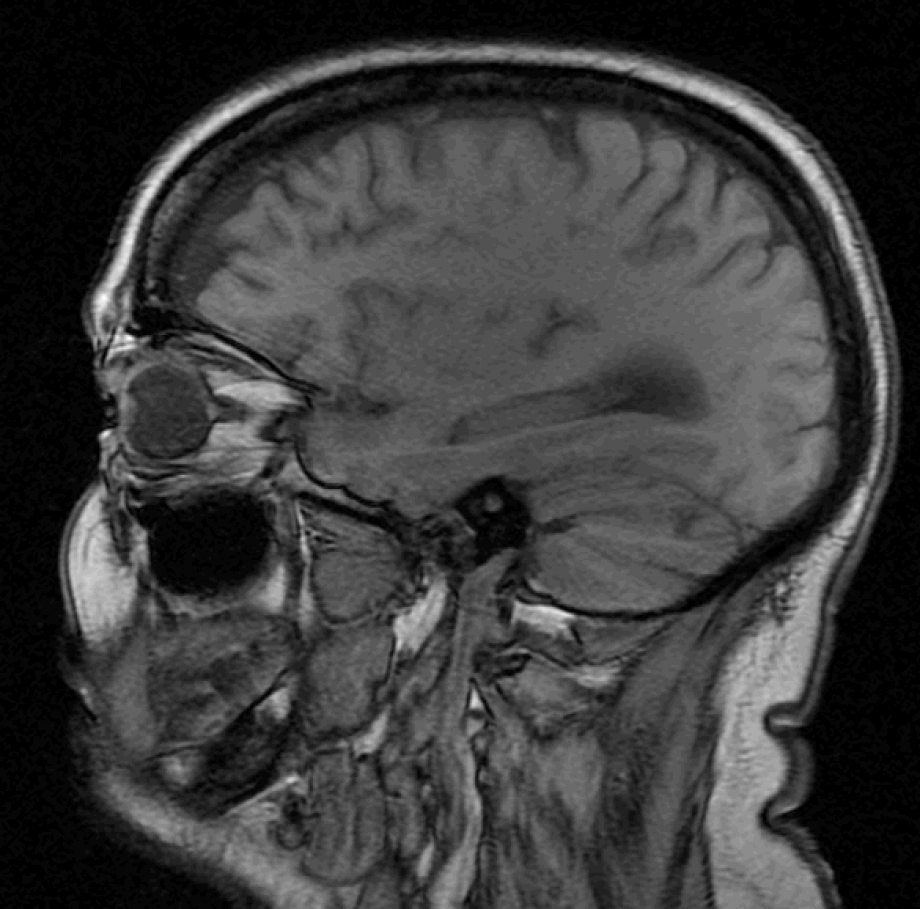

IRM, Scanner, radiographie, échographie, Doppler, Mammographie,Infiltration, Ponction et imagerie interventionnelle, Conebeam